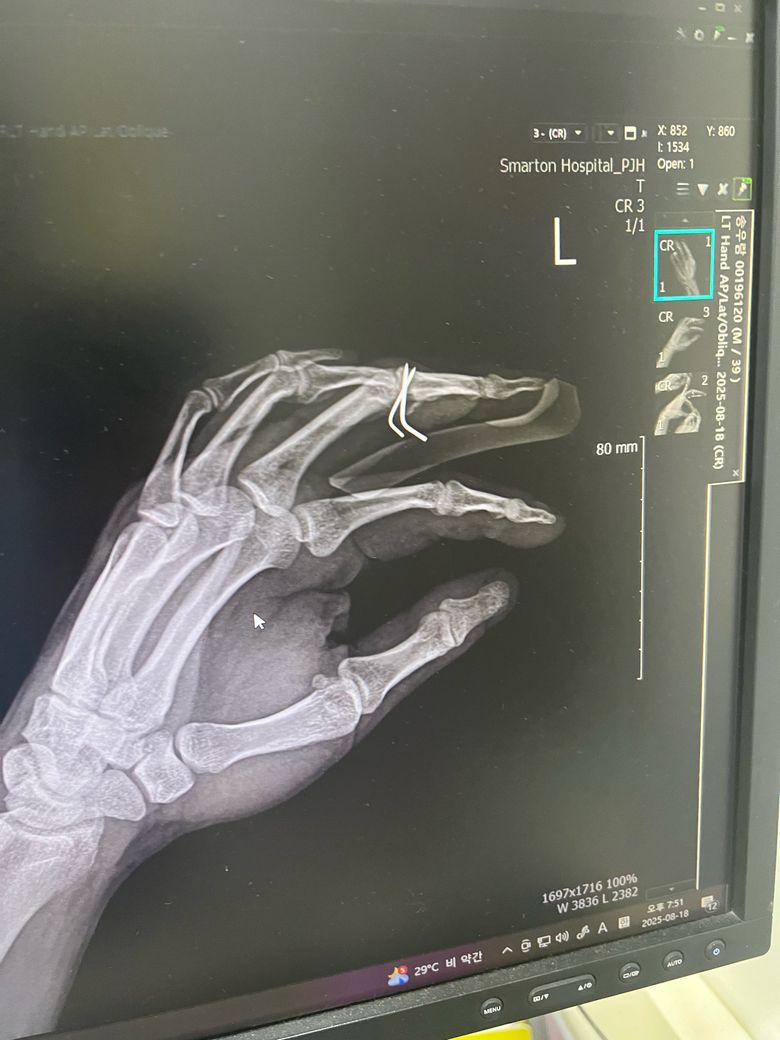

수술 전과 후 엑스레이 사진인데 잘 된건가요?

엑스레이상 핀만 박았지 골절나서 빠진 뼈부분은 그대로인거같아서요. 확인 좀 부탁드립니다. 그리고 혹시나 추후에 핀을 뽑을때는 어땋게 뽑나요

엑스레이상 핀은 골절 부위 고정으 위해 잘 박힌 것으로 보이지만 뼈 조각이 조금 남아 있는 경우도 있어 뼈가 자연적으로 붙을 때까지 관찰이 필요합니다.

수술 직후에는 일부 틈이 보여도 회복 과정에서 채워질 수 있어요 핀 제거는 작은 절개나 구멍을 통해 핀을 잡아 빼는 방식으로 간단하게 진행됩니다. 담당 의사가 뼈 유합 상태를 확인 후 안전하게 제거 시기를 결정합니다!